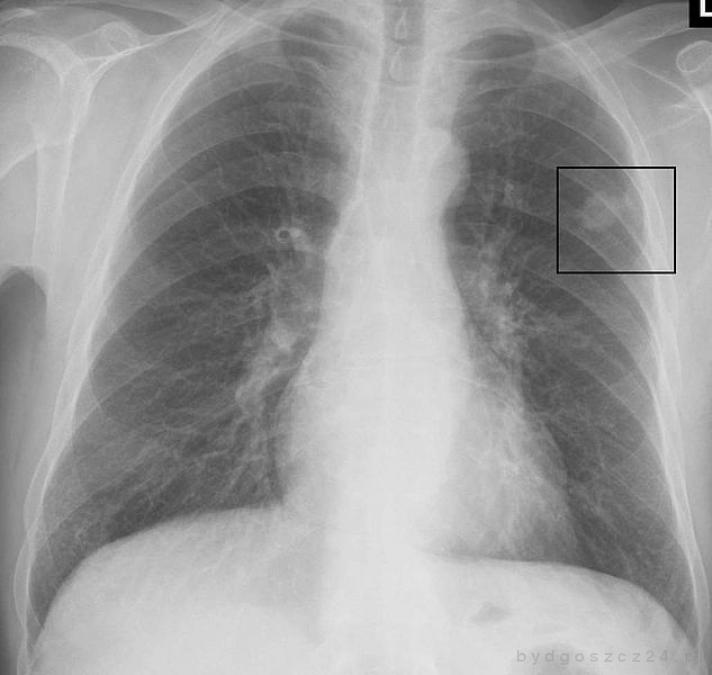

Doktor Małgorzata Czajkowska, stwierdziła ponadto, że na całym świecie wciąż poszukuje się skutecznej metody wczesnego wykrywania raka. Obecnie najlepiej zbadaną metodą wczesnej diagnostyki raka płuca pozostaje niskodawkowa tomografia komputerowa klatki piersiowej. Już w województwie zachodniopomorskim i pomorskim prowadzone są programy wczesnego wykrywania raka płuca za pomocą tej metody w grupie wysokiego ryzyka raka płuca, a więc u palaczy i byłych palaczy tytoniu po 50 roku życia. Wiadomo bowiem, że palenie czynne powoduje 20- krotny wzrost ryzyka zachorowania na raka płuca. U osób z POChP ryzyko raka płuca zwiększa się 4-krotnie.Najskuteczniejszą jednak metodą, która uchronić może palacza od rozwoju POChP czy raka płuca, jest rzucenie palenia. Dlatego tak ważną rolę przywiązujemy do pomocy palaczom w porzuceniu nałogu.